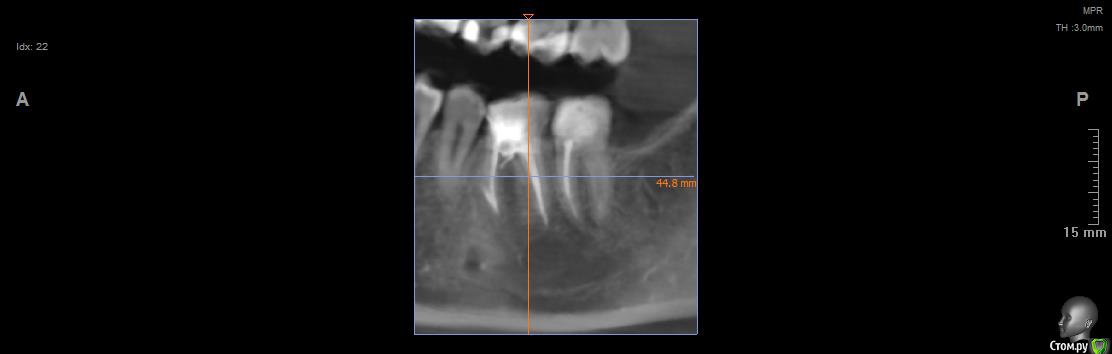

Vords Опубликовано 11 июня, 2020 Поделиться Опубликовано 11 июня, 2020 (изменено) Доброго вечера, профессионалы. Прошу у Вас помощи. Буду очень благодарен за консультацию. 3 недели назад появились боли в в жевательных зубах (около 37 и 36 зубов). В виду того, что боли были достаточно серьезные, а врач, у которого я лечился ранее не мог меня принять из-за пандемии - пришлось идти в городскую поликлинику. По результатам похода был поставлен диагноз пульпит 37 и глубокий кариес 36. На 36 поставили пломбу - 37 успешно депульпировали. На этом история 37 зуба закончена. С 36 после постановки пломбы начались дикие ночные боли и боли при накусывании. На повторном приеме был поставлен диагноз пульпит 36 - поставлено лекарство для умертвления нерва. После этого боль при накусывании прошли. В следующий прием пришел на чистку каналов и пломбировку. Во время этой процедуры я вдруг ощутил совершенно дикую боль (как выяснилось потом - в этот момент и произошла перфорации в области фуркации). Врач ничего не сказал - просто поставил метапекс и запломбировал каналы. В этот момент начались боли при накусывании. а потом постоянная тянущая боль. Продолжалось это около 3 дней - я пошел в другую стоматологию где мне сделали рентген и с подозрение на перфорацию отправили на КТ. По результатам КТ перфорация была подтверждена. С КТ я пришел в городскую стомотологию где мне предложили закрыть перфорацию цементом (pro что-то там - не могу сказать точно). Закрыли ее во вторник на этой неделе. Сегодня восстановили коронку и поставили световую пломбу. Беда в том, что боль при накусывании и "нытье" с этой стороны так и не прошли. По словам стомотолага гос клиники - боль при накусывании из-за метапекса и когда он рассосется - боль пройдет. (до 6 месяцев). Я прилагаю рентген (ужасное качество), фото КТ и ссылку в облако на КТ. Я допускаю, что никто не захочет лезть в облако и тратить свое время на просмотр на КТ (сам не могу разобраться с программой, что бы сделать достойные скрины), но если вдруг у кого-то найдется время - буду очень благодарен. Рентген сделан сразу после пломбировки канала. КТ через 3 дня после этого. В связи с этим вопрос. Возможно ли, что боль при надавливании пройдет если подождать пока рассосется метапекс или это пустая трата времени? Мне стоит ждать какое - то время или в этой ситуации мне поможет только удаление? Благодарю Вас за уделенное время Ссылка на КТ https://cloud.mail.ru/public/44WE/2JeTfXmr2 Изменено 11 июня, 2020 пользователем Vords Ссылка на комментарий

krokomot Опубликовано 11 июня, 2020 Поделиться Опубликовано 11 июня, 2020 Судя по всему у вас в 6м зубе выведен не только метапекс но и гуттаперчевый штифт, скорее всего, если это не исправить боли сохранятся, и что там с коронкой не понятно, на кт сильные тени из-за большого объема рентгеноконтрасного материалла, а прицельный снимок что вы сделали, сделан не поп правилам и на нем сильные искажения, понять трудно что с коронкой. Короче, зуб с перфорацией , выведенным материалом за апексом и гуттаперчей, и при этом еще и беспокоит, прогноз сомнительный. возможно всё можно переделать и всё станет нормально , но это не точно. Вам нужен грамотный доктор эндодонтист. 1 Ссылка на комментарий

wladdX Опубликовано 11 июня, 2020 Поделиться Опубликовано 11 июня, 2020 (изменено) Скриншоты Изменено 11 июня, 2020 пользователем wladdX 1 Ссылка на комментарий

Vords Опубликовано 11 июня, 2020 Автор Поделиться Опубликовано 11 июня, 2020 (изменено) WladdX, огромное спасибо Вам за потраченное на скрины время. А то я так и не смог освоить эту программу (рукалицо). У меня даже есть ощущение, что я вижу теперь штифт, о котором говорил krokomot (хотя и не факт)))) Изменено 11 июня, 2020 пользователем Vords Ссылка на комментарий